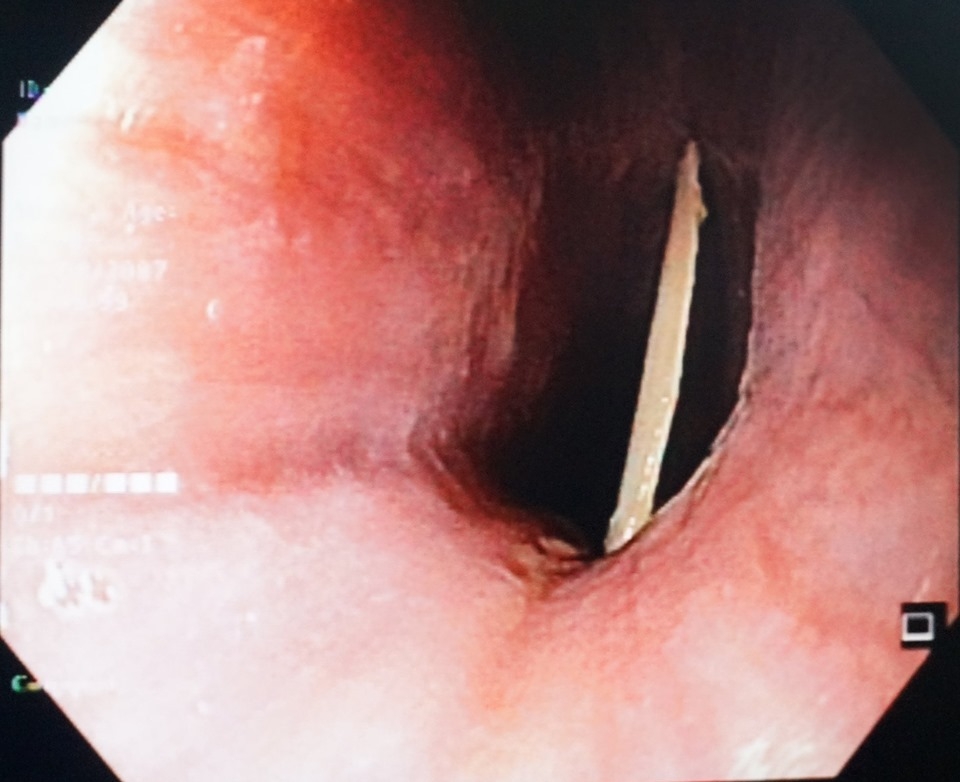

| Mảnh xương gà bị mắc ở thực quản bệnh nhân |

Ngay khi tiếp nhận và khai thác bệnh, ông L. được chỉ định nội soi thực quản. Kết quả cho thấy dị vật là mảnh xương gà bề ngang khoảng 2,5cm, 2 cạnh sắc nhọn nằm ngang cắm sâu 1/3 trên thực quản. Các bác sĩ Trung tâm Nội soi BVXA đã tiến hành gắp dị vật ra. Sau khi mảnh xương gà được gắp ra ngoài, cổ họng bệnh nhân không còn cảm giác đau rát nữa.